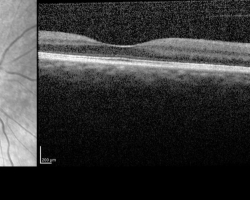

- OCT maculaire : montre l’œdème papillaire à droite mais l’objectif de l’examen est surtout d’éliminer une pathologie maculaire à l’origine de cette baisse d’acuité visuelle.

FO : cf. images jointes